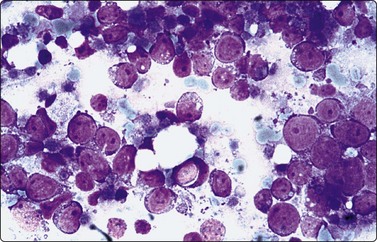

image image

Fig. 5.2 Small cell anaplastic carcinoma

Dispersed malignant cells with dense chromatin, irregular nuclear contour, nuclear molding, inconspicuous nucleoli and cytoplasm; note irregular cytoplasmic (B) and nuclear fragments in the background representing tumor necrosis (A and B) (MGG, HP).

Fine needle biopsy samples of lymphoid tissue, nodal or extranodal, benign or malignant, as a rule have a very high cell content. This is obvious to the naked eye as the aspirate is smeared. It looks like a film of slimy material which turns gray on drying. The cytoplasm of lymphoid cells is fragile. Many cells are represented by naked nuclei or have only a small rim of cytoplasm. A variable number of rounded cytoplasmic fragments measuring up to 8 microns in diameter are scattered in the background (Fig. 5.1). The cytoplasmic fragments were named ‘lymphoglandular bodies’ by Söderström. The term ‘lymphoid globules’ is prefered since they are present in smears from any lymphoid infiltration, not only from lymph nodes. The fragments stain an uniform pale blue, identical to the cytoplasm of intact cells, with Giemsa stain. They differ from necrotic debris by their regular round shape and their uniform staining. Necrotic debris and nuclear fragments (karyorrhexis and apoptotic bodies) are characteristic of smears of small cell undifferentiated carcinoma (Fig. 5.2). The recognition of ‘lymphoid globules’ is of diagnostic value in the distinction of lymphoma from anaplastic carcinoma and some other tumors.